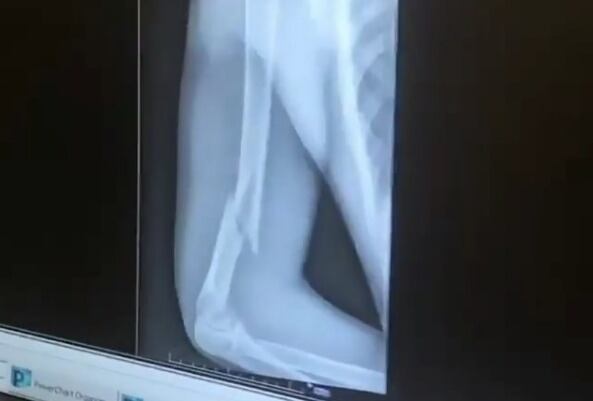

Según un video que publicó Fernán Vélez, conocido como “El Nalgorazzi”, se observa la grave fractura que tuvo el artista en su brazo derecho.

En la misma se ve que el intérprete de “Me niegas” tiene un hueso roto.